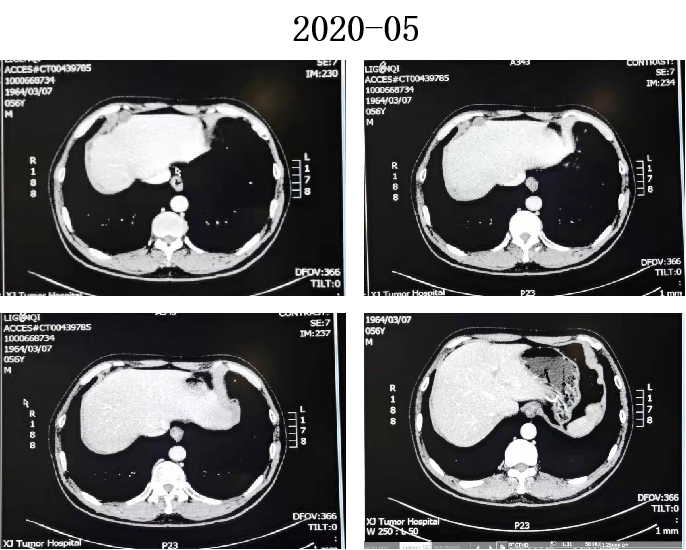

2020-03至2020-05月 5周期伊立替康+卡培他滨+贝伐珠单抗。

2020-04 复查CT:腹膜病变较前缩小。

2020-06 复查CT:腹盆腔少量积液,腹膜增厚,较前变化不大。因患者乏力及消化道反应,2020-06至2020-09 贝伐珠单抗+卡培他滨片。